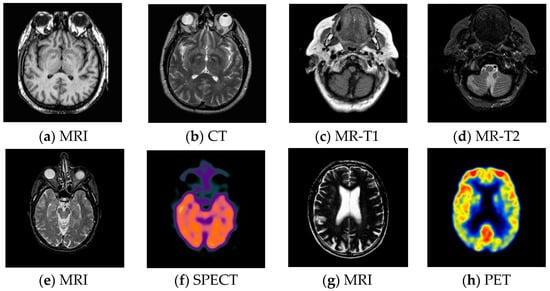

3.2. Test Images

For pixel level multi-modality medical image fusion, most of the test images generally can be obtained at http://www.imagefusion.org and http://www.med.harvard.edu/aanlib/home.html. To demonstrate the effectiveness of the proposed method, we utilize four pairs of real multimodal medical images shown in Figure 6 to evaluate the algorithm in our experiments, the size of all of them is 256 × 256, and all of them are perfectly registered, which means that the objects in each set of images are geometrically aligned. These medical images include MRI, CT, MR-T1, MR-T2, SPECT and PET, the characteristics of each of them are summarized as following.

Figure 6.

Pairs of medical source images: (a,b) MRI/CT images, (c,d) MR-T1/MR-T2 images; (e,f) MRI/SPECT images; (g,h) MRI/PET images.

- CT has a shorter imaging time and a higher spatial resolution, whereas it provides soft tissue information with low contrast.

- MRI can clearly display the soft tissue information of the human body, but it is hard to reflect the dynamic information of the metabolic activity in human body.

- MR-T1 image is sensitive to observe the anatomy, while the MR-T2 image can detect the tissue lesions.

- SPECT can show the biological activities of cells and molecules, but it is difficult to distinguish human organ tissues due to the low image quality of SPECT.

- PET can reflect the metabolic activity information of human tissues and organs at the molecular level, but the spatial resolution of PET is relatively low.